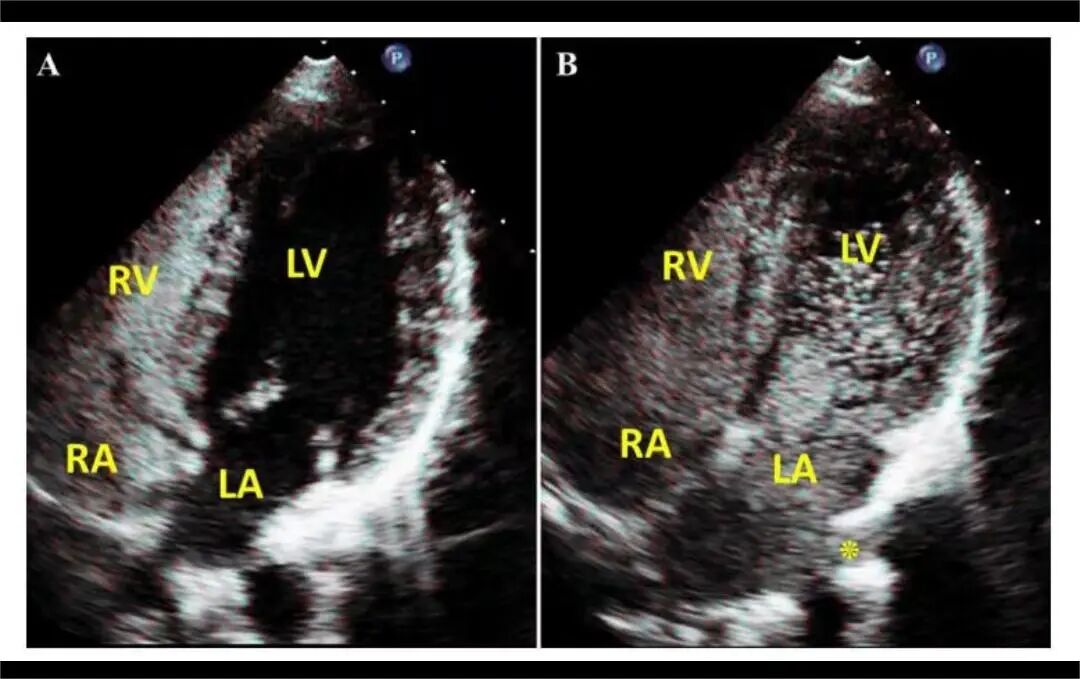

1月7日,贵州航天医院第91次晨读会由我院超声科医师杨向蓉作学术交流,她以“小微泡,大作用——右心声学造影”为题,详细讲解了右心声学造影的基本原理、适用情况、操作方式及心脏异常分流评估特点等内容,涵盖了该技术的实施条件、所用造影剂类型及多种激发试验方法,并通过多个病例图文资料分享了右心声学造影在相关症状病因探寻中的辅助角色,为临床评估提供了一种观察途径,有助于从循环角度了解某些症状的可能原因,在相应症状的病因分析中具有一定的参考意义。 贵州航天医院 超声科专家简介 吴艳辉 中共党员,超声科学科带头人,主任医师 专业擅长:从事超声诊断工作30余年,对心血管、小器官超声、超声引导下介入等具有丰富的临床经验。 胡大海 超声科主任,副主任医师 专业擅长:从事超声工作20余年,对心血管、外周血管、浅表器官、成人颅脑、超声造影诊断及超声引导下介入等具有丰富的临床经验。 骆科美 中共党员,超声科副主任医师 专业擅长:从事超声诊断工作30余年,对胎儿心脏及颅脑、妇产超声诊断、盆底超声等具有丰富的临床经验。 刘 敏 超声科副主任医师 专业擅长:从事超声诊断工作20余年,对妇产科超声、心脏血管超声诊断具有丰富的临床经验。 韩锡铁 超声科副主任医师 专业擅长:从事超声诊断近20年,对心血管、外周血管、浅表器官、肌骨神经超声诊断具有丰富的临床经验。 杨向蓉 中共党员,超声科主治医师 专业擅长:从事超声诊断工作16年,擅长心血管、浅表器官、盆底、腹直肌超声、右心声学造影及超声引导介入等技术。 贵州航天医院超声科简介 基本情况 贵州航天医院超声科配备多种超声检查设备(飞利浦彩超(IU-22、IU-Elite、EPIQ5、EPIQ7),迈瑞彩色超声(ResonaI9T、RechoR9、Resona I9、DC-8)、GE-VolusonE8、汕头SIUIAPogee6800、床旁彩色超声诊断仪等),设有心血管诊室、外周血管诊室、妇产科诊室、腹部诊室、绿色通道、浅表小器官等检查室。 诊疗范围 科室业务覆盖腹部、泌尿、妇科、产科(常规、NT筛查、系统筛查及高危妊娠监护)、成人心脏、外周血管、浅表器官(包含甲状腺、乳腺、阴囊、眼睛等)、颅脑(小儿颅脑、成人帕金森辅助筛查)、小儿肺超、超声造影、盆底、腹直肌、肌骨神经等检查及各种超声介入引导。 专科特色 四肢血管超声检查、产前系统筛查及超声监护、超声造影检查技术、介入超声临床应用、经颅脑实质超声辅助筛查诊断帕金森病、小儿髋关节筛查、女性性早熟超声诊断、盆底、腹直肌超声检查等。 NT超声检查 超声介入引导 肝脏超声造影 甲状腺造影 颅脑超声帕金森辅助检查 乳腺超声造影 上肢动静脉造瘘超声检查 双胎超声筛查 下肢血管超声检查 右心造影 end